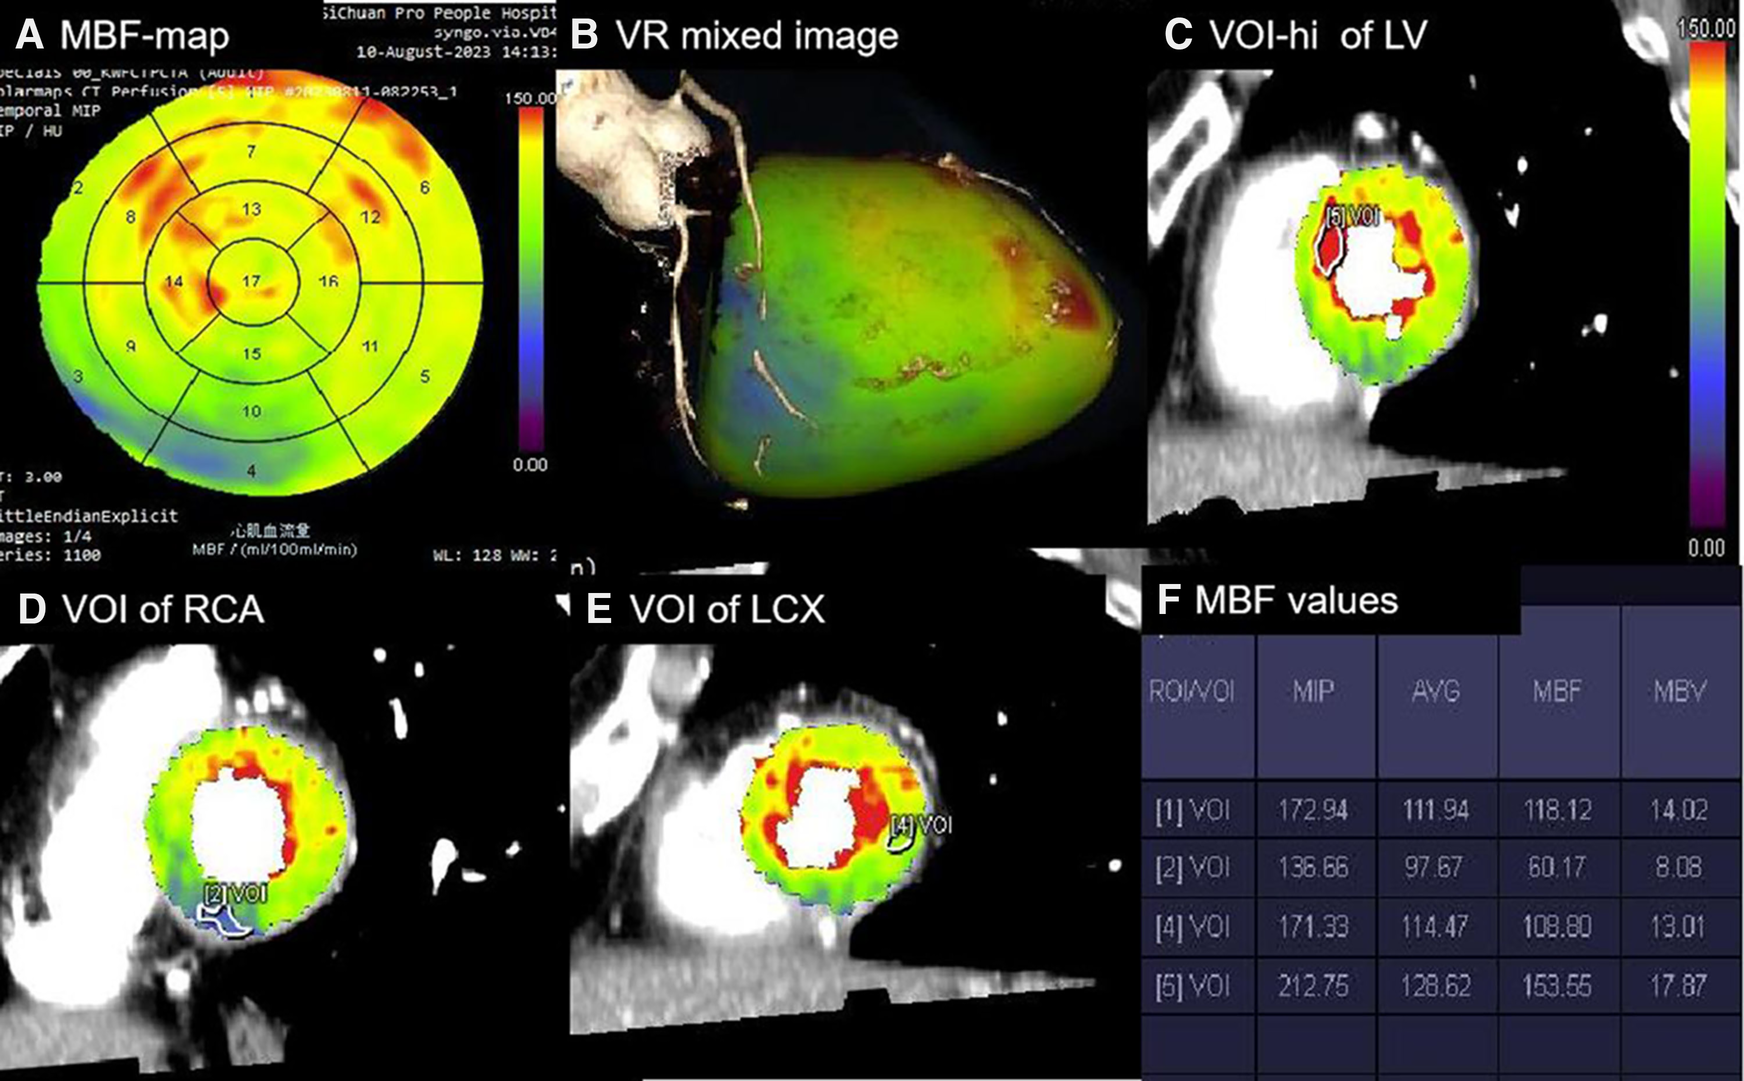

The lowest MBF values within the per-vessel territory and the highest MBF (MBF-hi) and average MBF (MBF-global) values of the LV were automatically calculated. The MBF-ratio was determined using the following equation: MBF-ratio = lowest MBF value/reference MBF value. In the per-patient analysis, the MBF-ratio was calculated as MBF-ratio = MBF-global value/MBF-hi value; in the per-vessel analysis, it was calculated as MBF-ratio = lowest MBFa value in the per-vessel territory/MBF-hi value. VOI processing is shown in Figure 1.

Figure 1

Processing of absolute and relative MBF values. (A) Polar map of MBF showing the MBF values in 1–17 segments with a color-coded scale. (B) Mixed-volume rendering image of CCTA combined with MBF showing the cardiac segments of three coronary artery territories. (C) VOI [5] with a minimum size of 0.5 cm2 manually delineated in the highest perfusion regions of the LV in the short-axis images. (D) VOI [2] delineated in the lowest region of the RCA territory. (E) VOI [4] delineated in the lowest region of the LCX territory. (F) Perfusion parameters automatically calculated for all VOIs [1], referring to the average perfusion of the LV. The MBF-ratio values could then be determined using the following equation: MBF-ratio = lowest MBF value/reference MBF value. RCA, right coronary artery; LCX, left circumflex artery.